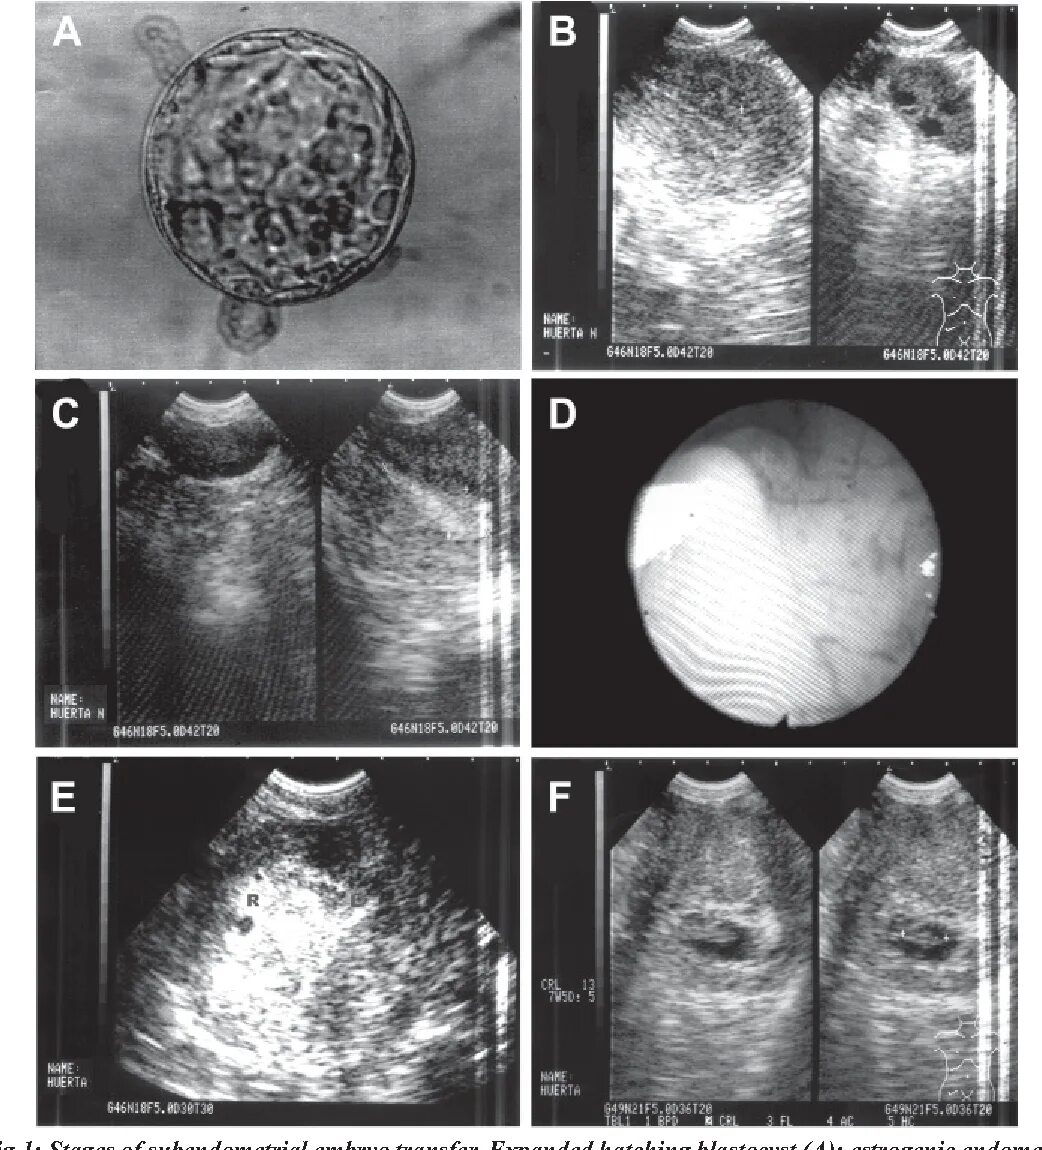

Имплантация эмбриона при эко форум